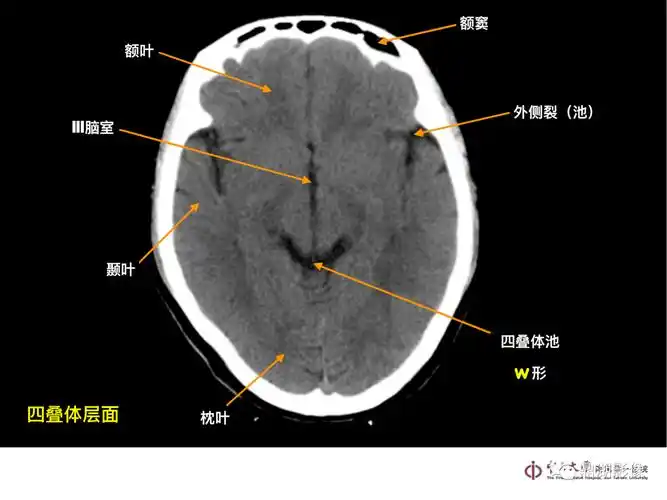

10张图搞定正常头颅ct断层解剖

头颅ct断层解剖

超实用急诊头颅ct3b阅片法

解剖颅脑ct断层中英文对照干货满满

头颅ct 解剖图谱,人手一份

头颅ct断层解剖图谱分享,如何书写诊断报告?全是干货 - 哔哩哔哩